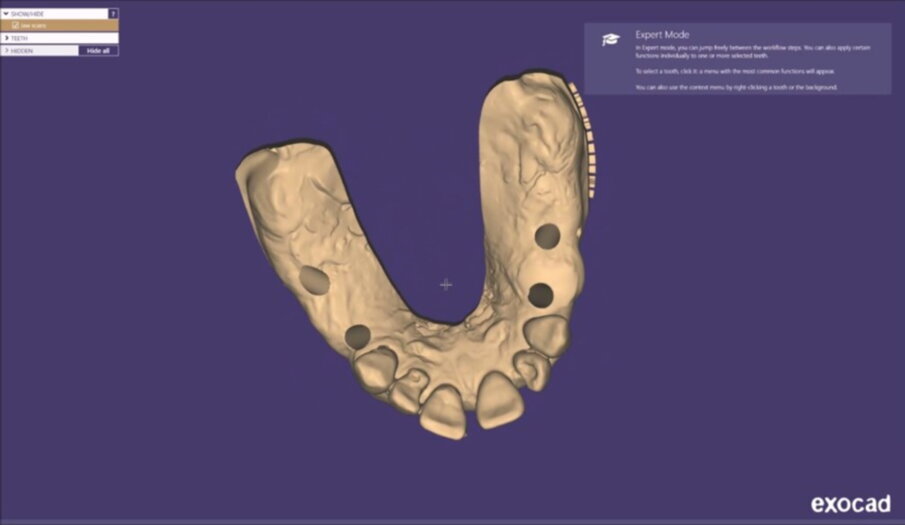

Figg. 13, 14_File STL ottenuti tramite scanner intraorale.

Figg. 21-25_Progettazione Cad con exocad.